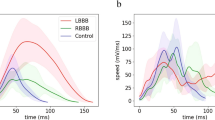

Patient baseline characteristics is presented in Table 1. Study population mean age was 65.4 ± 6.1 years with a numerically higher number of males among all participants (70%). All patients had LBBB morphology on the ECG with mean QRS duration 168 ± 17 ms. Using the 3D electro-mechanical NOGA XP system, a total of 8200 endocardial mapping points was evaluated in the 30 HFrEF patients (273 ± 47 mapping points per patient, around 30 min per patient) and EM parameters were calculated (Fig. 1a,b and “Methods”).

Based on quantitative (clockwise [< − 3°]/counterclockwise [> 3°]) and qualitative (apex-base relative rotation) analysis of LV rotation at each endocardial mapping point, patients were classified as: wringing rotation (Group A, Fig. 2a, Supplementary Fig. S2A, Supplementary Video S1); rigid body-type rotation (Group B), clockwise (Fig. 2b, Supplementary Fig. S2b, Supplementary Video S2) or counterclockwise (Fig. 2c, Supplementary Fig. S2c, Supplementary Video S3).

Intergroup comparisons between the two groups showed significant difference between all the sectors (Supplementary Table S2). Group B showed no change in average rotation angle across the apex, medial and basal sector. Due to the wringing motion in Group A, significant differences were observed between apical vs. medial sector (p = 0.016), and apical vs. basal ones (p < 0.0001) (Fig. 3a, Supplementary Table S3).

As per rotation velocity, intergroup comparisons showed significant differences at the medial sector (p = 0.003, Supplementary Table S2). Group B did not show intragroup sectorial differences, whilst Group A showed significant difference between apex vs. medial sectors (p = 0.001) and apex vs. basal ones (p = 0.042).

After filtering of the mapping points and assessment of an adequate catheter-endocardium contact, data were exported for analysis of rotation angles using external software algorithms. Rotational parameters were calculated by recording angular displacement of the individual mapping points around the heart axis, defined by the geocenter of all mapping points and the apex of the heart. The position of each mapping point was recorded in three dimensions at 10 ms intervals over a period of three heart cycles. Rotational values were calculated between LV end-diastolic to end-systolic phase. Similarly, local activation time (LAT), local rotational electro-mechanical delay (LEMD) and total rotational electro-mechanical delay (TEMD) were computed as shown in Fig. 1a. Acquired mapping points were positioned on the two-dimensional 9-segment model of the LV (bulls-eye projection, Fig. 1b) according to the corresponding tridimensional point coordinates. We divided the LV bulls-eye projection in four basal segments (basoseptal, basolateral, posterobasal, anterobasal), four mid-ventricular (midseptal, midlateral, midposterior, midanterior), and one apical segment. Each segment contains an averaged value of the parameter of interest in that position. These nine segments values were further aggregated in three sectors (apex, medial and basal sector) or across the whole LV to allow multilevel analysis (see Supplementary Fig. S1 online). When viewed in projection from the LV apex, clockwise rotation was labeled as a negative value, whereas a counterclockwise rotation as a positive value.

High resolution bullseye plots were obtained by oversampling segmental values by a factor 100, then these were interpolated with spline method and plotted in a polar graph by a custom script in Matlab R2017a (MathWorks, Natick, MA, USA), as shown in Fig. 3.